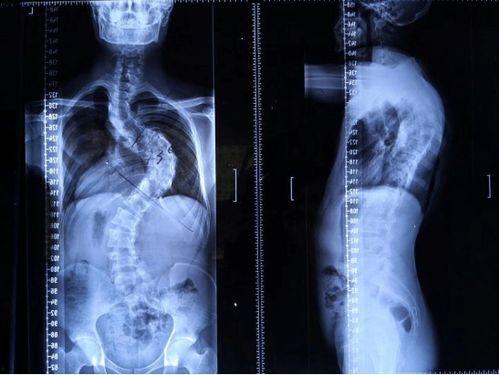

脊柱矫正,顾名思义,就是通过各种方法来调整脊柱的形态,使其恢复到正常状态。这个过程可能涉及到物理治疗、按摩、针灸、手术等多种手段。那么,成人还能矫正脊柱吗?答案是肯定的!

脊柱矫正的原理其实很简单,就是通过外力来改变脊柱的受力点,从而逐步调整脊柱的形态。这个过程需要耐心和毅力,因为脊柱矫正并非一蹴而就的事情。

脊柱矫正的效果因人而异,但一般来说,经过一段时间的治疗,大部分患者的脊柱都会得到明显改善。具体效果如下:

1. 缓解疼痛:脊柱矫正可以缓解因脊柱弯曲引起的疼痛。

2. 改善姿势:脊柱矫正可以帮助改善不良的姿势,使身体更加挺拔。

3. 提高生活质量:脊柱矫正可以改善患者的睡眠质量,提高生活质量。

成人矫正脊柱并非遥不可及的梦想,只要选择正确的方法,坚持治疗,你一定可以拥有一个健康的脊柱。所以,如果你正为脊柱弯曲而烦恼,不妨试试脊柱矫正吧!相信我,你会收获意想不到的惊喜!